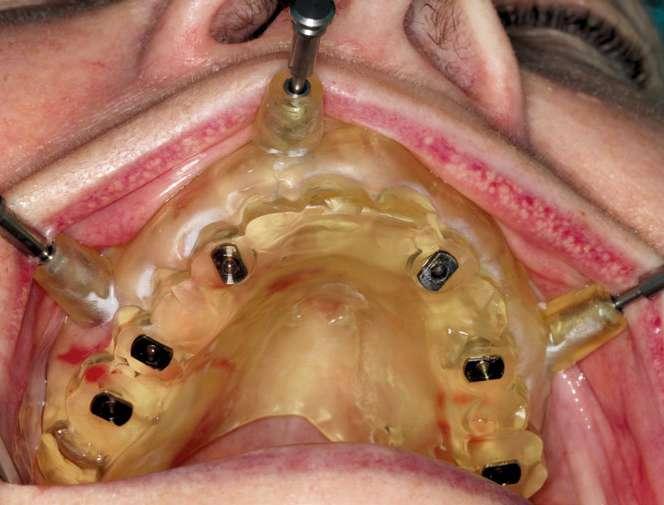

La paciente presentaba una Clase III de Cawood y Howell con una cresta alveolar con adecuada anchura y altura por lo que planificamos la colocación de seis implantes. No consideramos necesario añadir más implantes a nuestra planificación puesto que se trataba de una arcada cuadrada con un mínimo cantilever anterior. Además, se planificaron tres tornillos de anclaje para proporcionar una seguridad adicional. Diseñamos una férula quirúrgica para un procedimiento de fresado piloto guiado que guía la fresa espiral de 1,5 y 2,0 mm.

Antes de llevar a cabo la cirugía, es importante verificar que la apertura bucal de la paciente es de 40 mm como mínimo para acomodar el instrumental de la cirugía guiada.

Seleccionamos implantes NobelActive® con cambio de plataforma integrado que desplaza el micro gap hacia dentro en sentido horizontal, alejando las filtraciones bacterianas del hueso y una conexión cónica que proporciona estabilidad a la unión de implante pilar. Además, gracias a las herramientas de planificación del software podemos predecir de antemano qué pilares intermedios vamos a necesitar. (Fig. 6, 7 y 8).

A la hora de la cirugía, una vez verificada que la plantilla está en la posición correcta, fresamos a través del tubo del tornillo de anclaje mediante la fresa espiral guiada de 1,5 mm x 20 mm hasta el tope de la fresa e introducimos los tornillos de anclaje guiados completamente dentro del tubo. En este caso, hicimos un abordaje con colgajo, realizamos el fresado piloto guiado utilizando las fresas guiadas seleccionadas según el informe del plan de tratamiento, seguidamente retiramos la plantilla quirúrgica y continuamos con la preparación de los lechos y la colocación de los implantes. Se utilizó la secuencia recomendada por el fabricante en hueso tipo III para colocar los implantes. Los torques de inserción finales fueron entre 32 y 50 Nw.